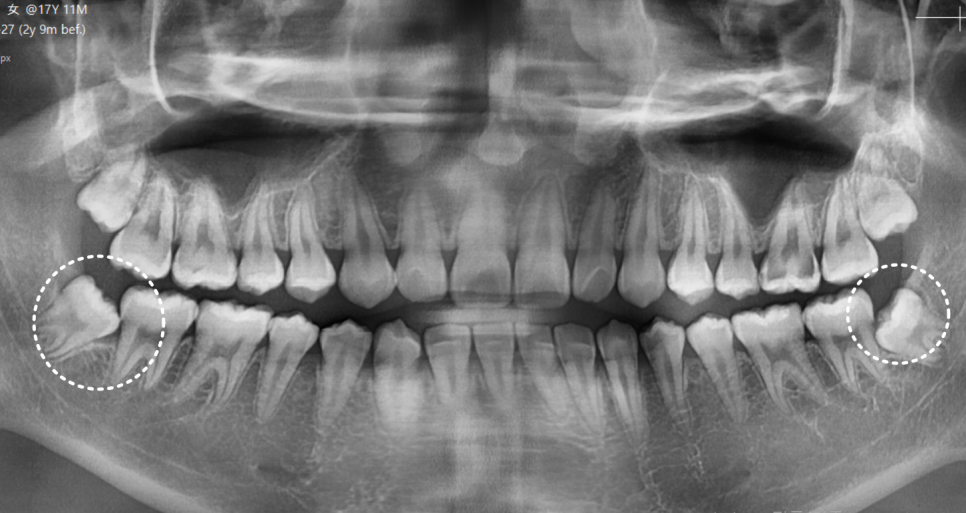

내원 당시 살펴보니

사랑니는 비스듬히 누워 반쯤만

잇몸 밖으로 나온 상태였습니다.

240919

문제는 사랑니 자체보다

바로 앞어금니 상태였습니다.

엑스레이와 입안 사진을 통해 확인해 보니,

230227(전) 240919 (후)

1년 반 사이에 사랑니뿐만 아니라,

앞에 치아까지 충치가 생겨있었습니다.

심지어 충치가 꽤나 많이 진행되어

이미 신경 가까이까지 진행된 상황이었습니다.